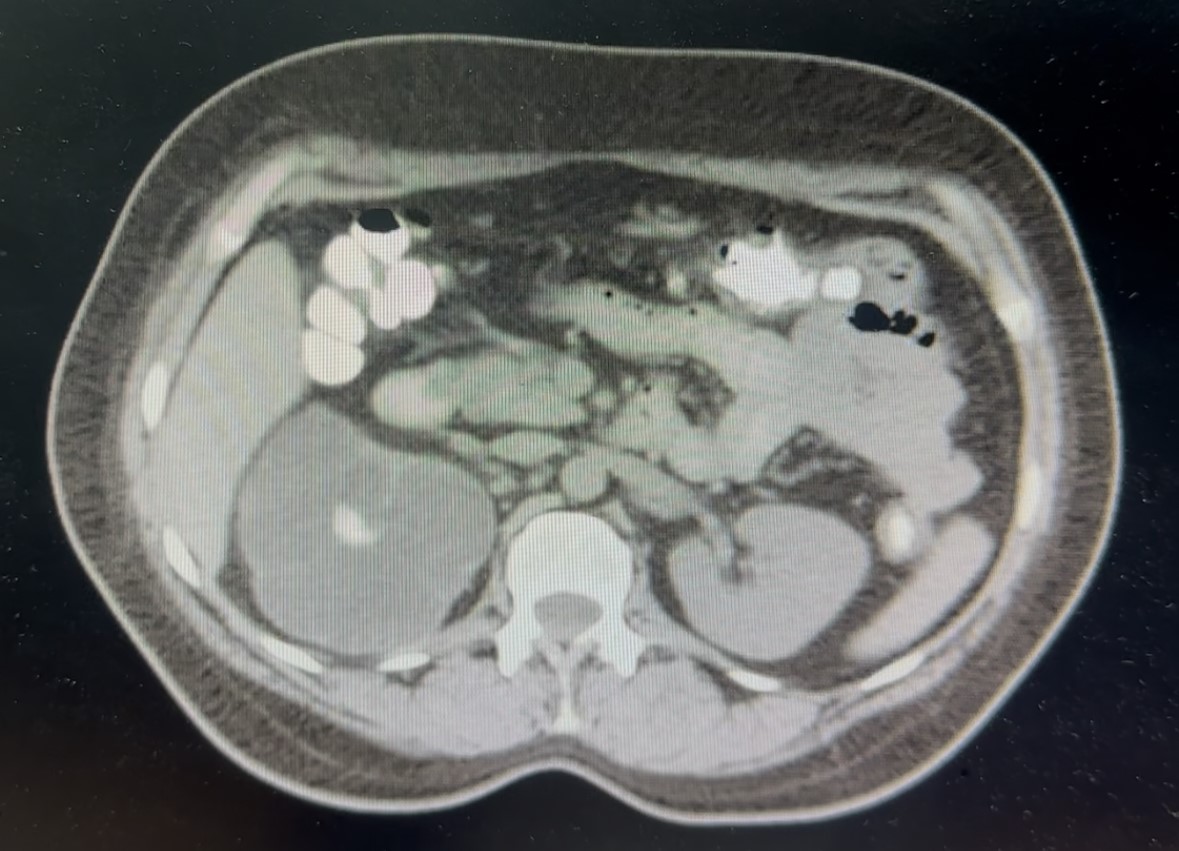

TOMOGRAFÍA COMPUTARIZADA

El hallazgo llamativo del estudio lo condiciona la presencia de hidronefrosis severa del riñón derecho (Figura 2) que se asocia a importante disminución del grosor cortical y signos de dilatación pielocalicial, que es condicionado por la presencia de una imagen hiperatenuante que ocupa completamente la pelvis y los cálices renales, adoptando una morfología ramificada (Figura 3a) y muestra densidad heterogénea mayormente hiperdensa que oscila entre los 950 y 1280 UH. El hallazgo sugiere obstrucción urinaria prolongada con probable compromiso funcional del parénquima renal (Figura 3b).

Imagen 2: Tomografía axial del abdomen y pelvis. Se observa adelgazamiento cortical y pérdida de la diferenciación corticomedular del riñón derecho por severa hidronefrosis, hallazgos sugerentes de daño estructural renal crónico. Compárese con la morfología conservada del riñón contralateral. Fuente: departamento de radiología médica del Hospital Regional Dr. Rafael Hernández.